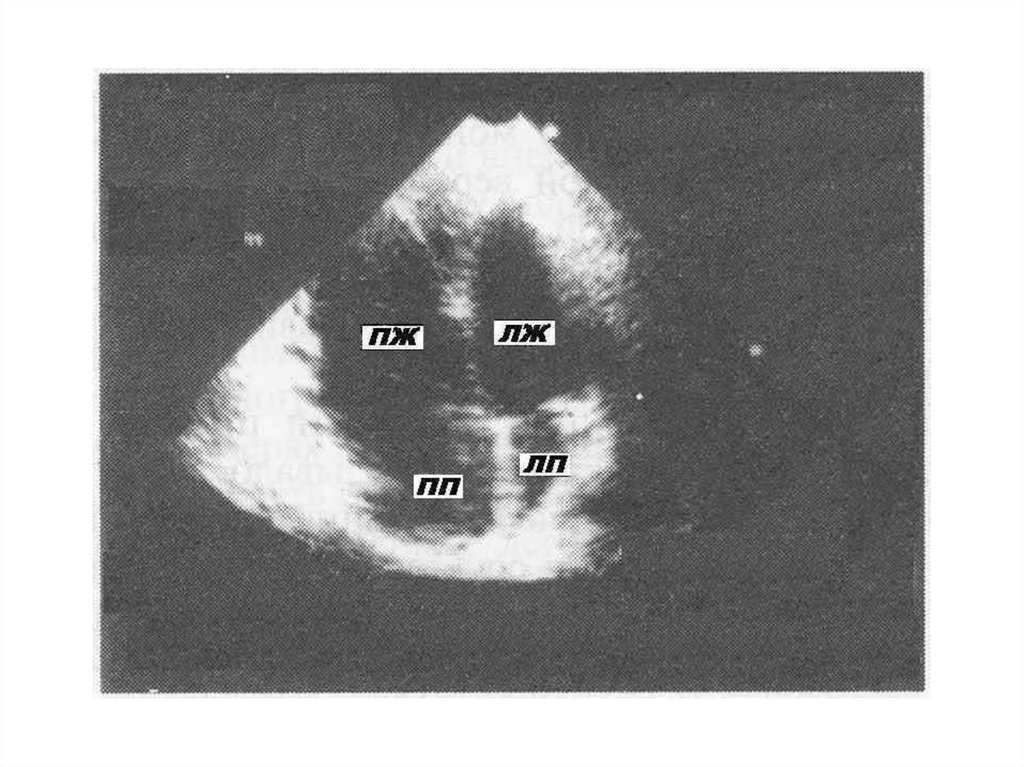

40. ЭхоКГ изменения при остром МКТ:

а) лёгкое течение:

• ЭхоКГ картина может быть нормальной; или

• небольшая дилатация полости и дисфункция ЛЖ (снижение

систолической экскурсии стенок, небольшое снижение ФВ);

б) тяжёлое течение:

• резкое снижение ФВ;

• может быть снижение сократимости сегментарного характера;

• несоответствие между резко выраженным снижением

сократимости и небольшой степенью дилатации полостей

(отличие от ДКМП);

• обратимое увеличение толщины стенок ЛЖ (отёк);

• пристеночные тромбы в полости ЛЖ на фоне гипокинезии

миокарда и эндокардита;